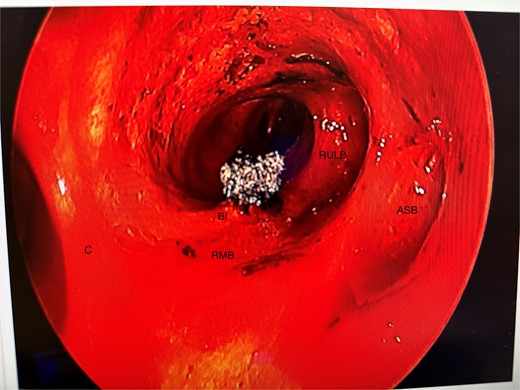

She initially underwent a rigid bronchoscopy, biopsy of the endobronchial tumour, cryoablation, and argon plasma for debulking. On direct visualization with the telescope the tumour was polypoid and was arising from the membranous portion of the right main bronchus (RMB) (Fig. 2).

Initial rigid bronchoscopy showing a polypoid mass originating from the membranous portion of the right main bronchus; BI, bronchus intermedius; RMB, right main bronchus.

Anomalous right bronchial anatomy was also noted (Fig. 3). The biopsy was sent for frozen section, which confirmed a carcinoid tumour.

Post disobliteration of the tumour through rigid bronchoscopy, also showing aberrant anatomy, where the apical segmental bronchus of the right upper lobe has a high take off at the distal trachea/carina; C, carina; RMB, right main bronchus; BI bronchus intermedius; RULB, right upper lobe bronchus; ASB, apical segmental bronchus.